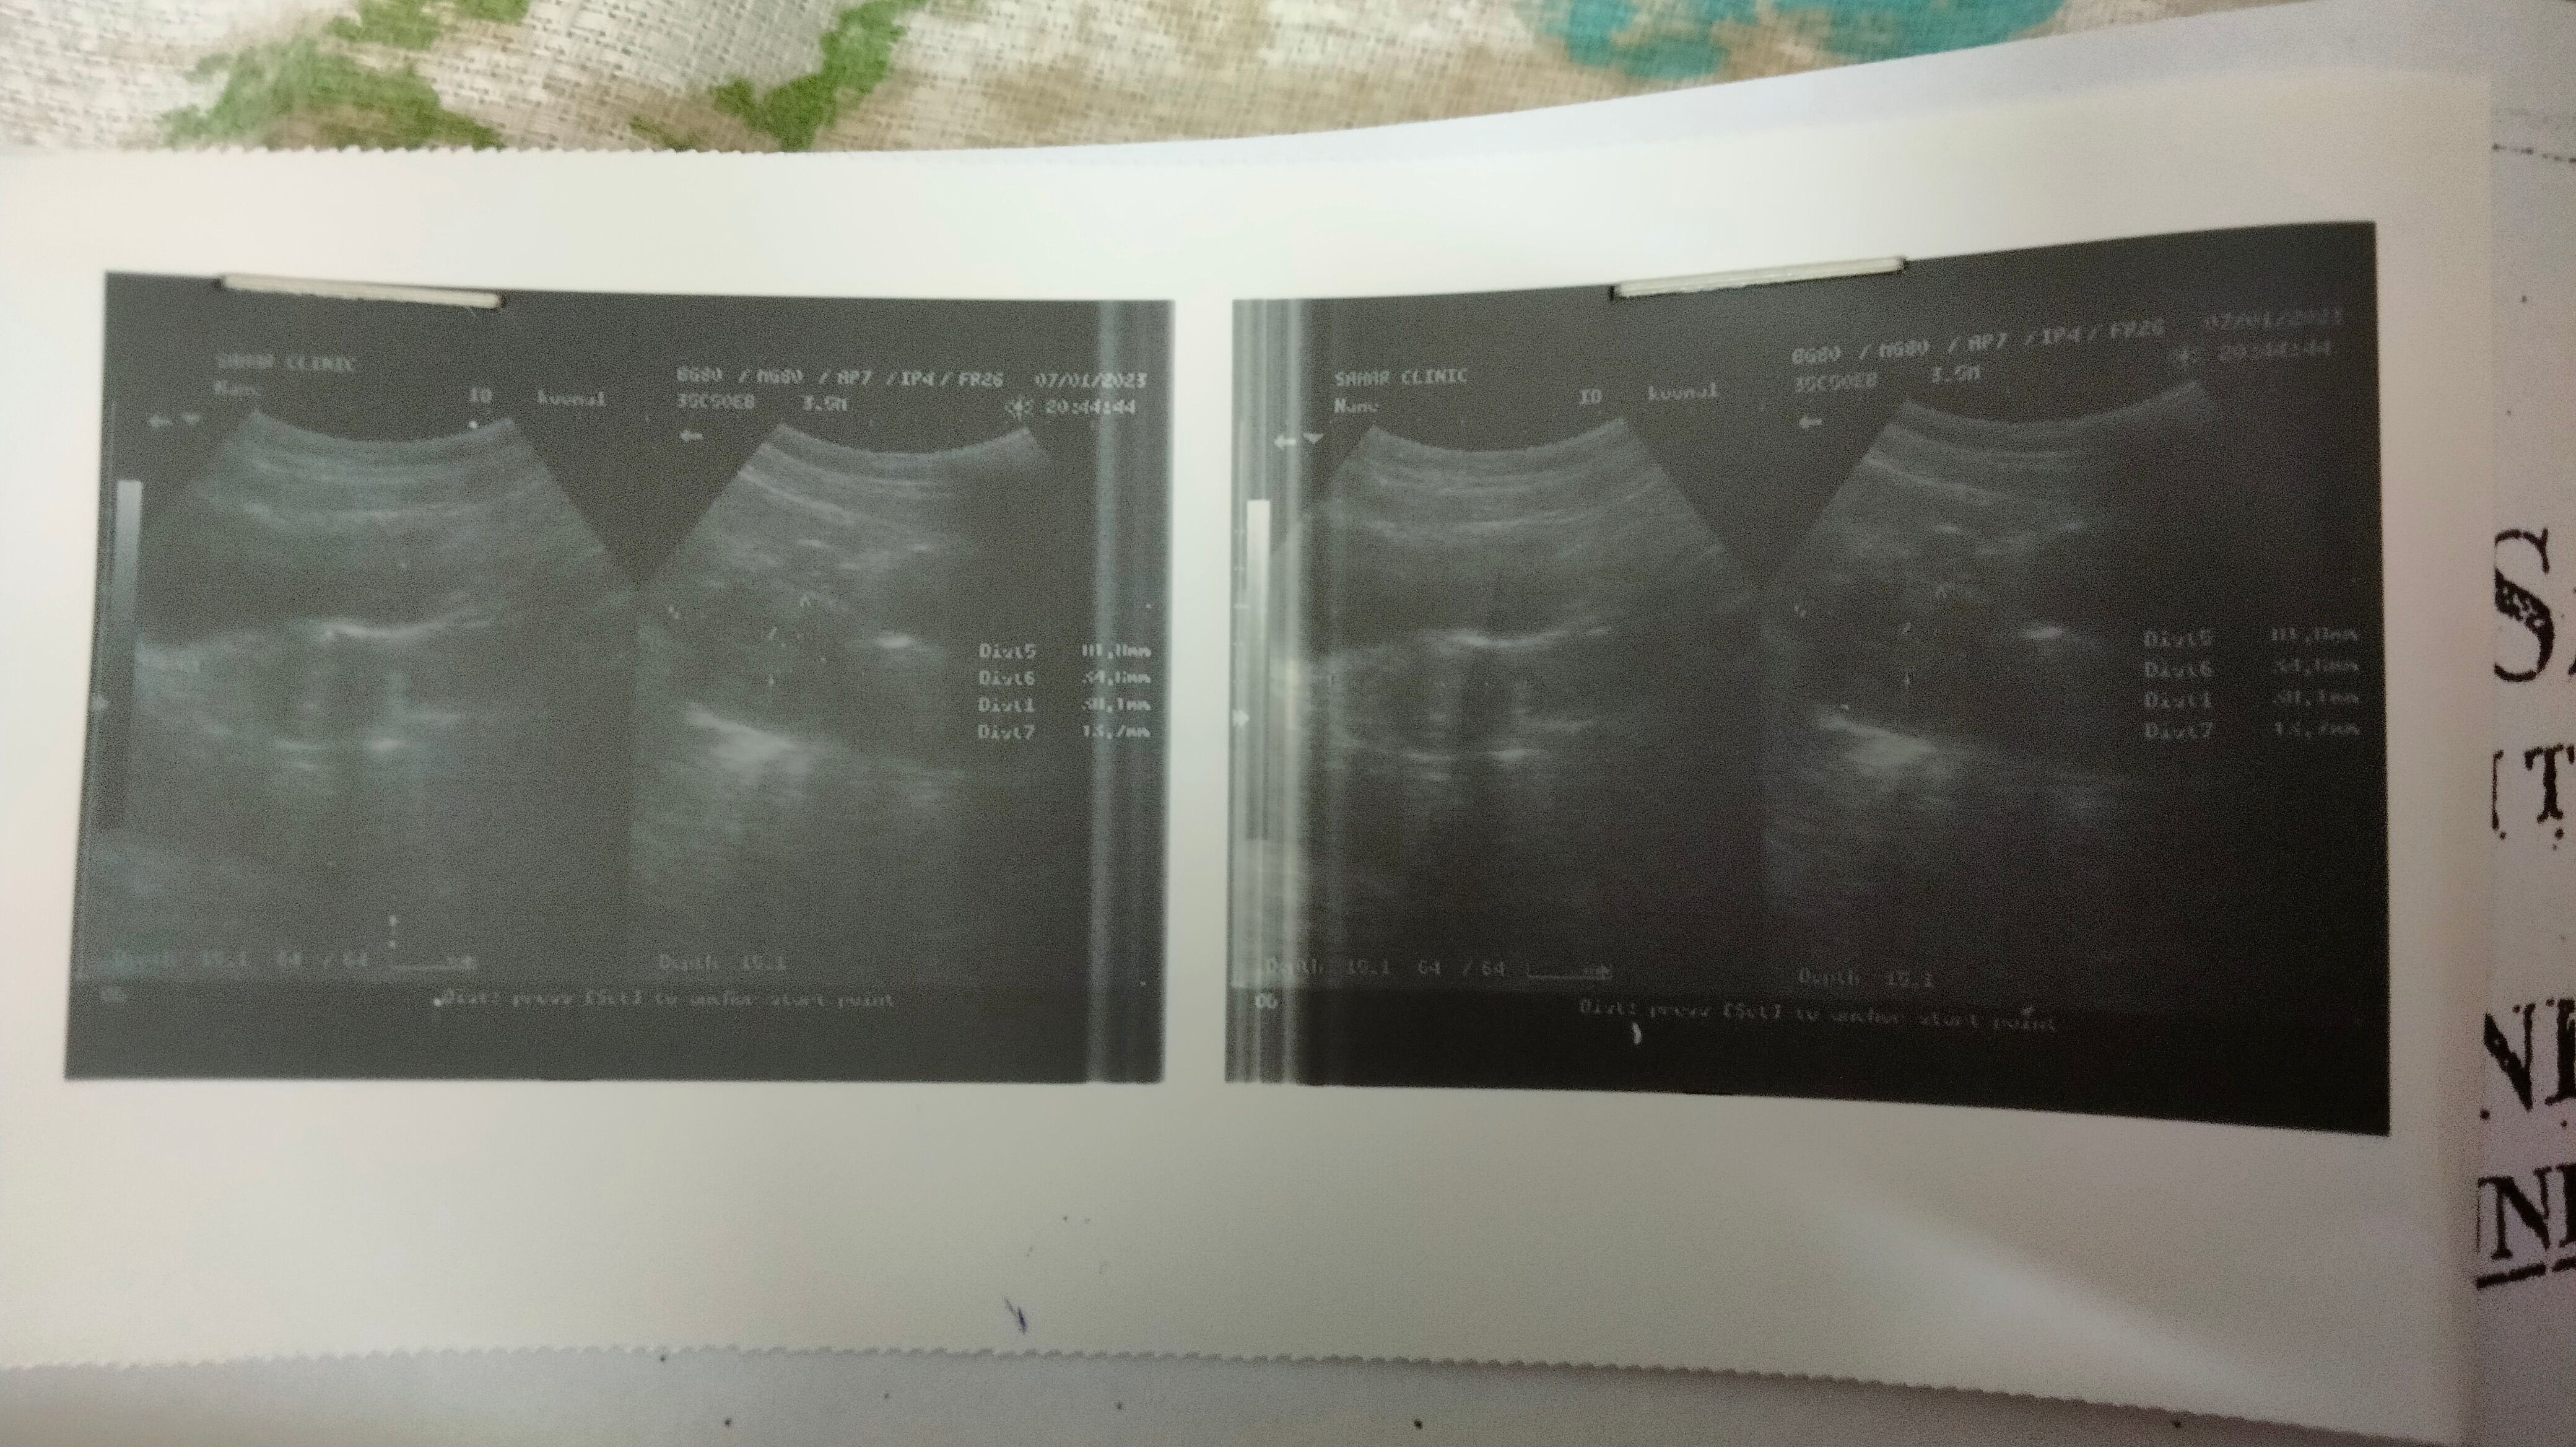

Dr ny Kaha tha mjhy abdominal pain hrha th sbha s meny AJ ultrasound kreaya to ye report aai h ap kch Dekh k Btaden SB normal h or ye report dkhlen kindly

Report